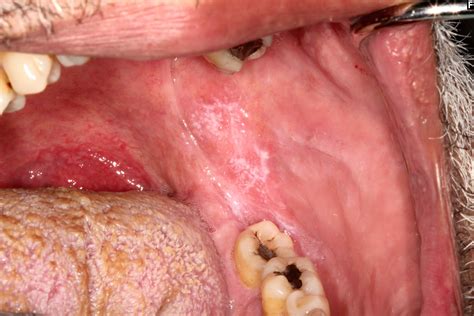

The primary symptom that sets this condition apart is the intense pain associated with the erosions. Patients often describe a burning sensation that intensifies when they consume acidic, spicy, or hot foods. The appearance can be quite alarming, often presenting as:

• Bright red patches: Areas where the outer layer of the mucosal lining has been shed.

• Ulcerations: Open, raw sores that bleed easily.

• White striae: Lacy, web-like white lines surrounding the red or ulcerated areas.

• Gingival involvement: Often manifesting as desquamative gingivitis, where the gum tissue appears raw and peels away.